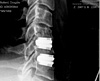

I almost forgot - here’s my X-rays of “after”. Ignore the lean in the forward-facing X-ray - I was doing what my radiologist told me to do, I don’t normally lean like that!

Post op side_sm

Two days after surgery - note that the rather sinister “hooks” at the front of the vertebrae are gone.